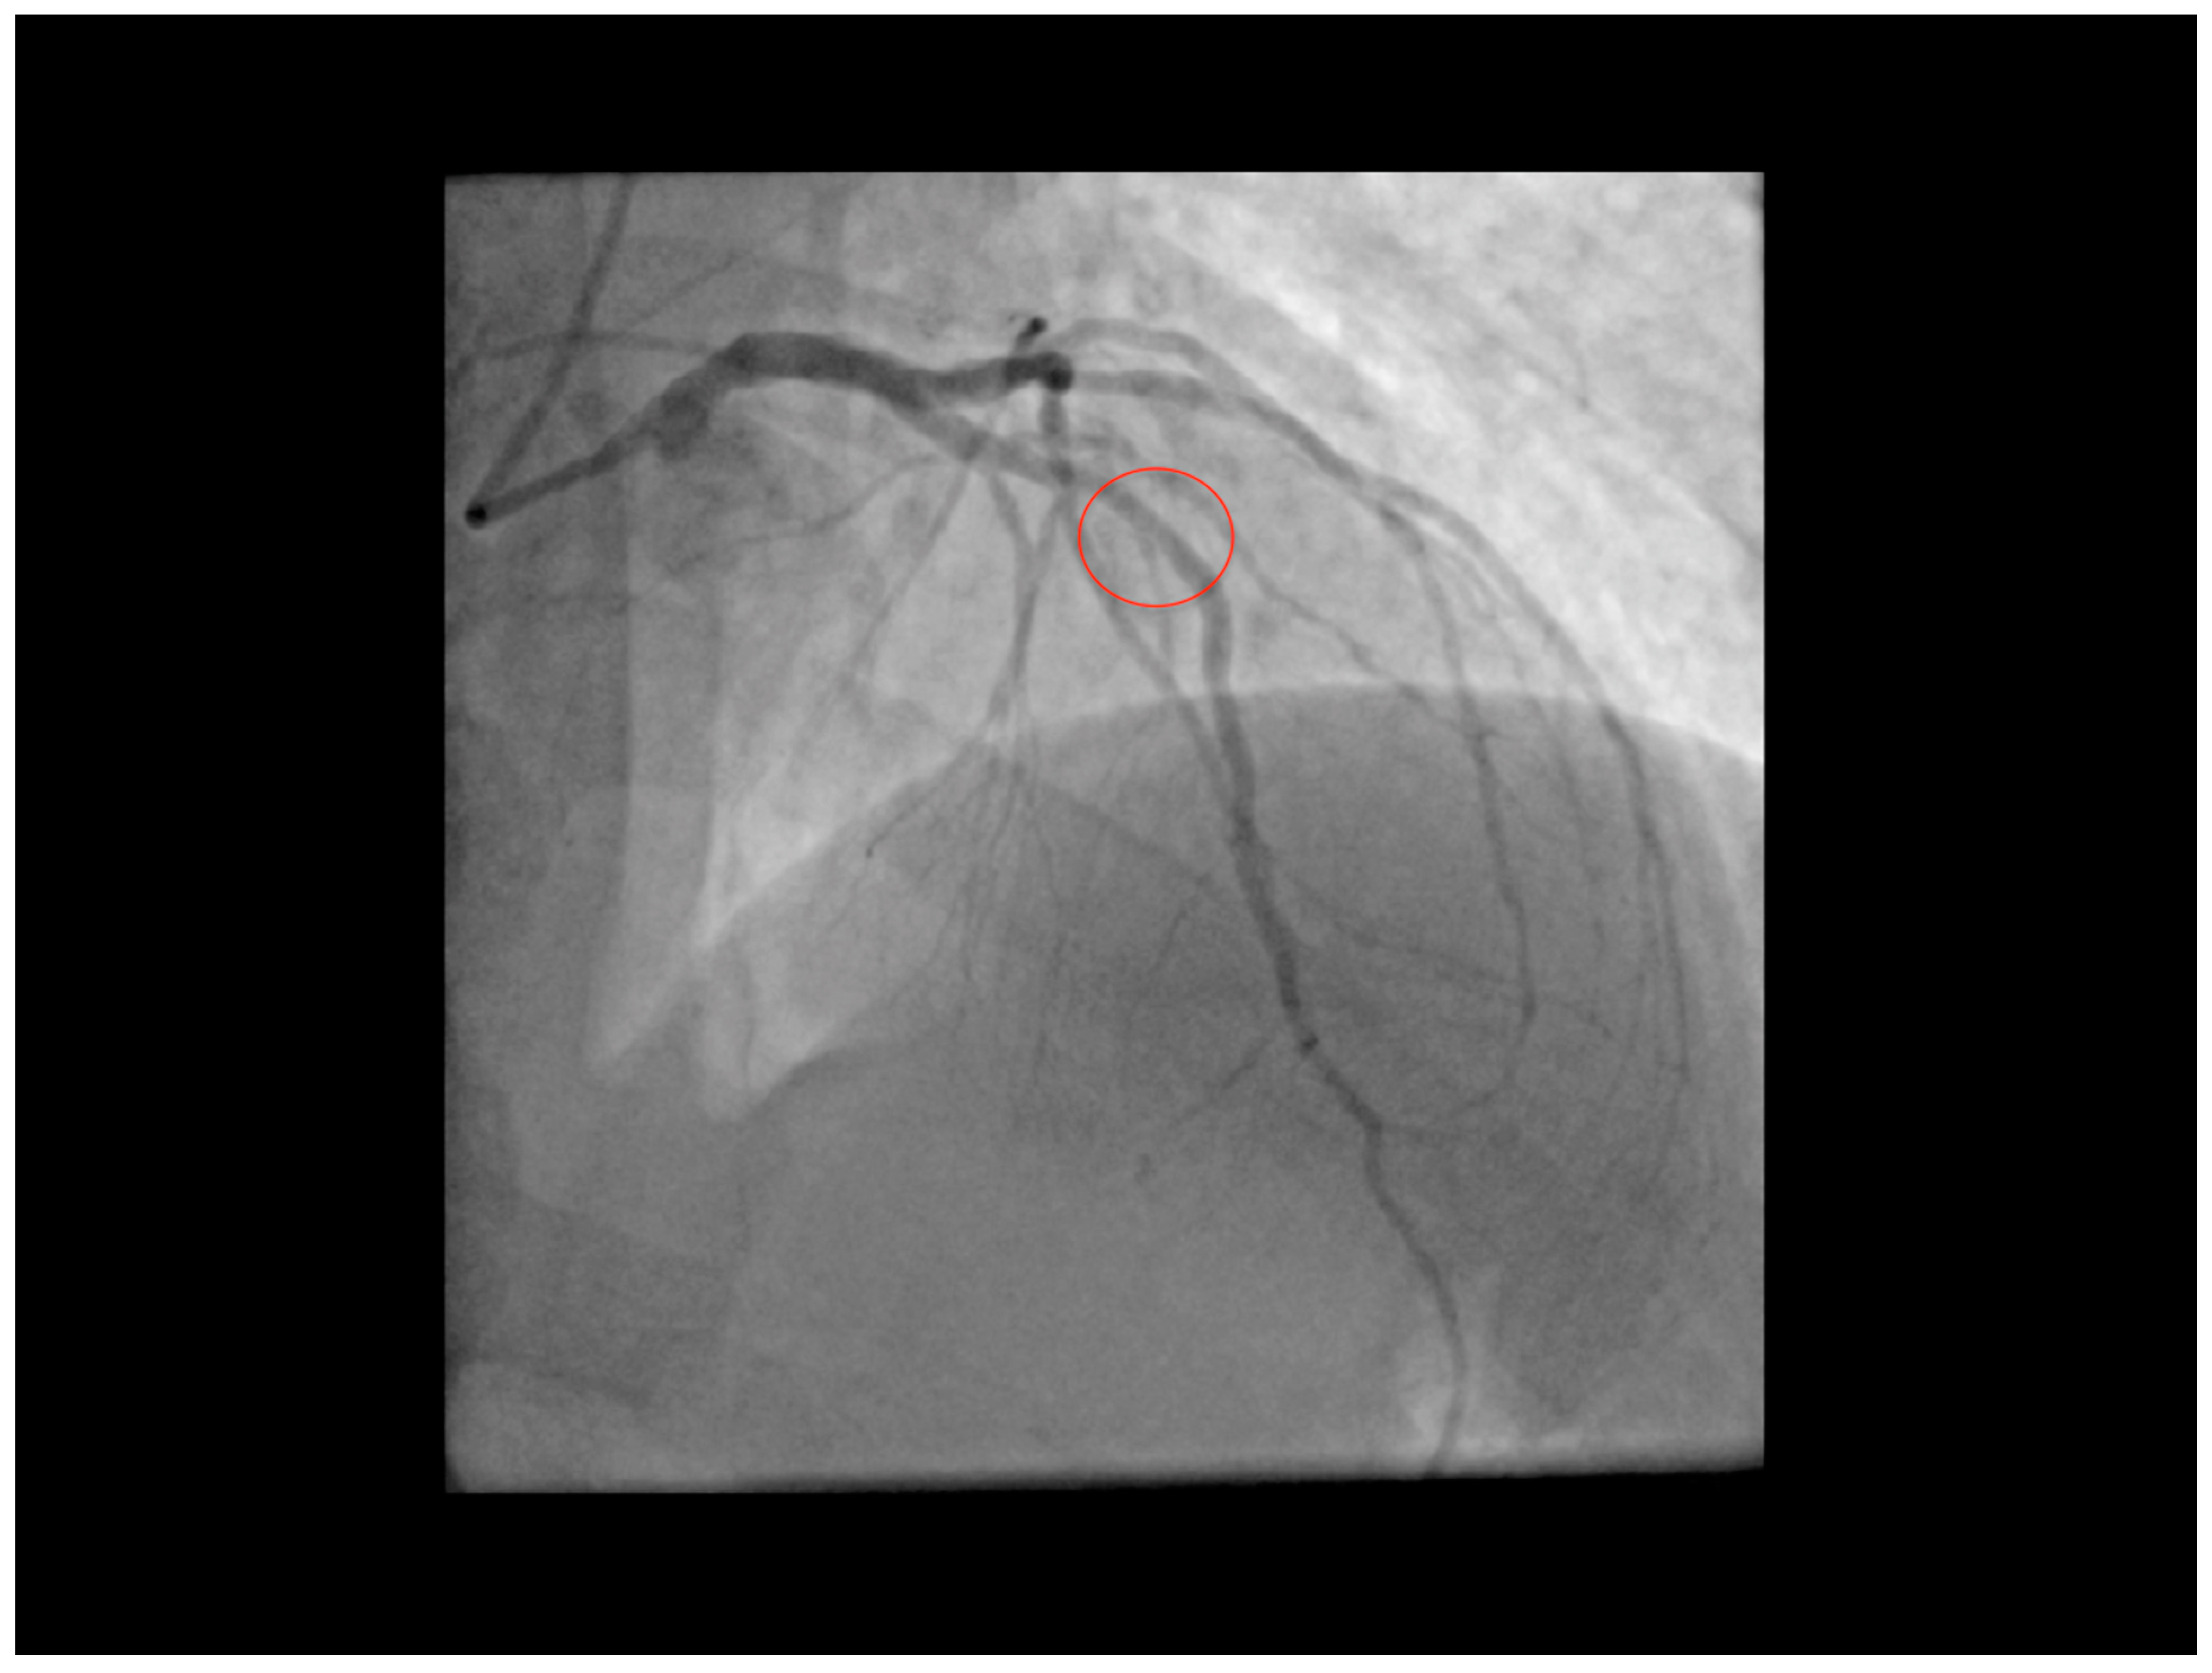

2. The Case

3.2. Computed Tomography Angiography